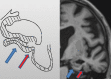

Neurodegenerative diseases are a devastating group of disorders that can be difficult to accurately diagnose. Although these disorders are difficult to manage owing to relatively limited treatment options, an early and correct diagnosis can help with managing symptoms and coping with the later stages of these disease processes. Both anatomic structural imaging and physiologic molecular imaging have evolved to a state in which these neurodegenerative processes can be identified relatively early with high accuracy. To determine the underlying disease, the radiologist should understand the different distributions and pathophysiologic processes involved. High-spatial-resolution MRI allows detection of subtle morphologic changes, as well as potential complications and alternate diagnoses, while molecular imaging allows visualization of altered function or abnormal increased or decreased concentration of disease-specific markers. These methodologies are complementary. Appropriate workup and interpretation of diagnostic studies require an integrated, multimodality, multidisciplinary approach. This article reviews the protocols and findings at MRI and nuclear medicine imaging, including with the use of flurodeoxyglucose, amyloid tracers, and dopaminergic transporter imaging (ioflupane). The pathophysiology of some of the major neurodegenerative processes and their clinical presentations are also reviewed; this information is critical to understand how these imaging modalities work, and it aids in the integration of clinical data to help synthesize a final diagnosis. Radiologists and nuclear medicine physicians aiming to include the evaluation of neurodegenerative diseases in their practice should be aware of and familiar with the multiple imaging modalities available and how using these modalities is essential in the multidisciplinary management of patients with neurodegenerative diseases.©RSNA, 2020.